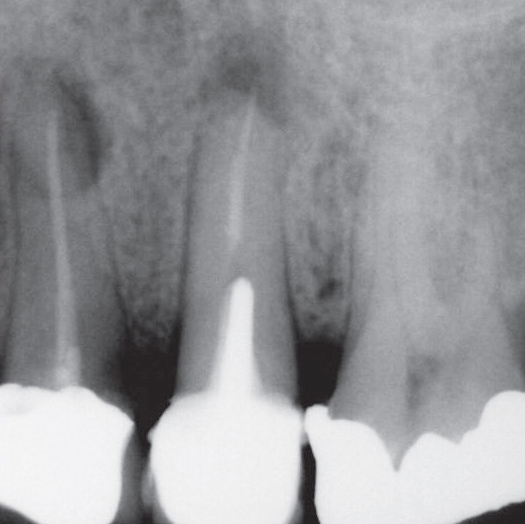

After

After Root Canal treatment